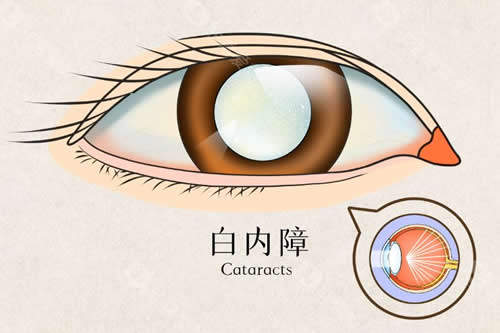

呼和浩特市针对白内障患者推出的免费手术政策,以“光明行”系列项目为核心,覆盖65岁以上户籍老人及低收入困难群体,提供免费筛查、手术及部分费用兜底确保,政策持续至2028年12月。本文将从政策背景、覆盖人群、申请条件、执行流程等维度,拆解核心权益与实操要点,助力符合条件者顺利享受活动。

基于第七次国境内人口普查数据,呼市常住人口344.61万人,65岁以上老年群体占比达13.83%,总量约50万人。而中华医学组织眼科学分会的统计显示,我国60岁以上人群白内障发病率约80%,庞大的患病基数让政策延续成为民生刚需。

医学层面,申请者需经专科诊断确诊为白内障,且裸眼视力≤0.3或矫正视力<0.5,这一标准是判断手术必要性的核心依据。同时需排除相关禁忌症,例如活动性眼部感染、未控制的全身性疾病等。